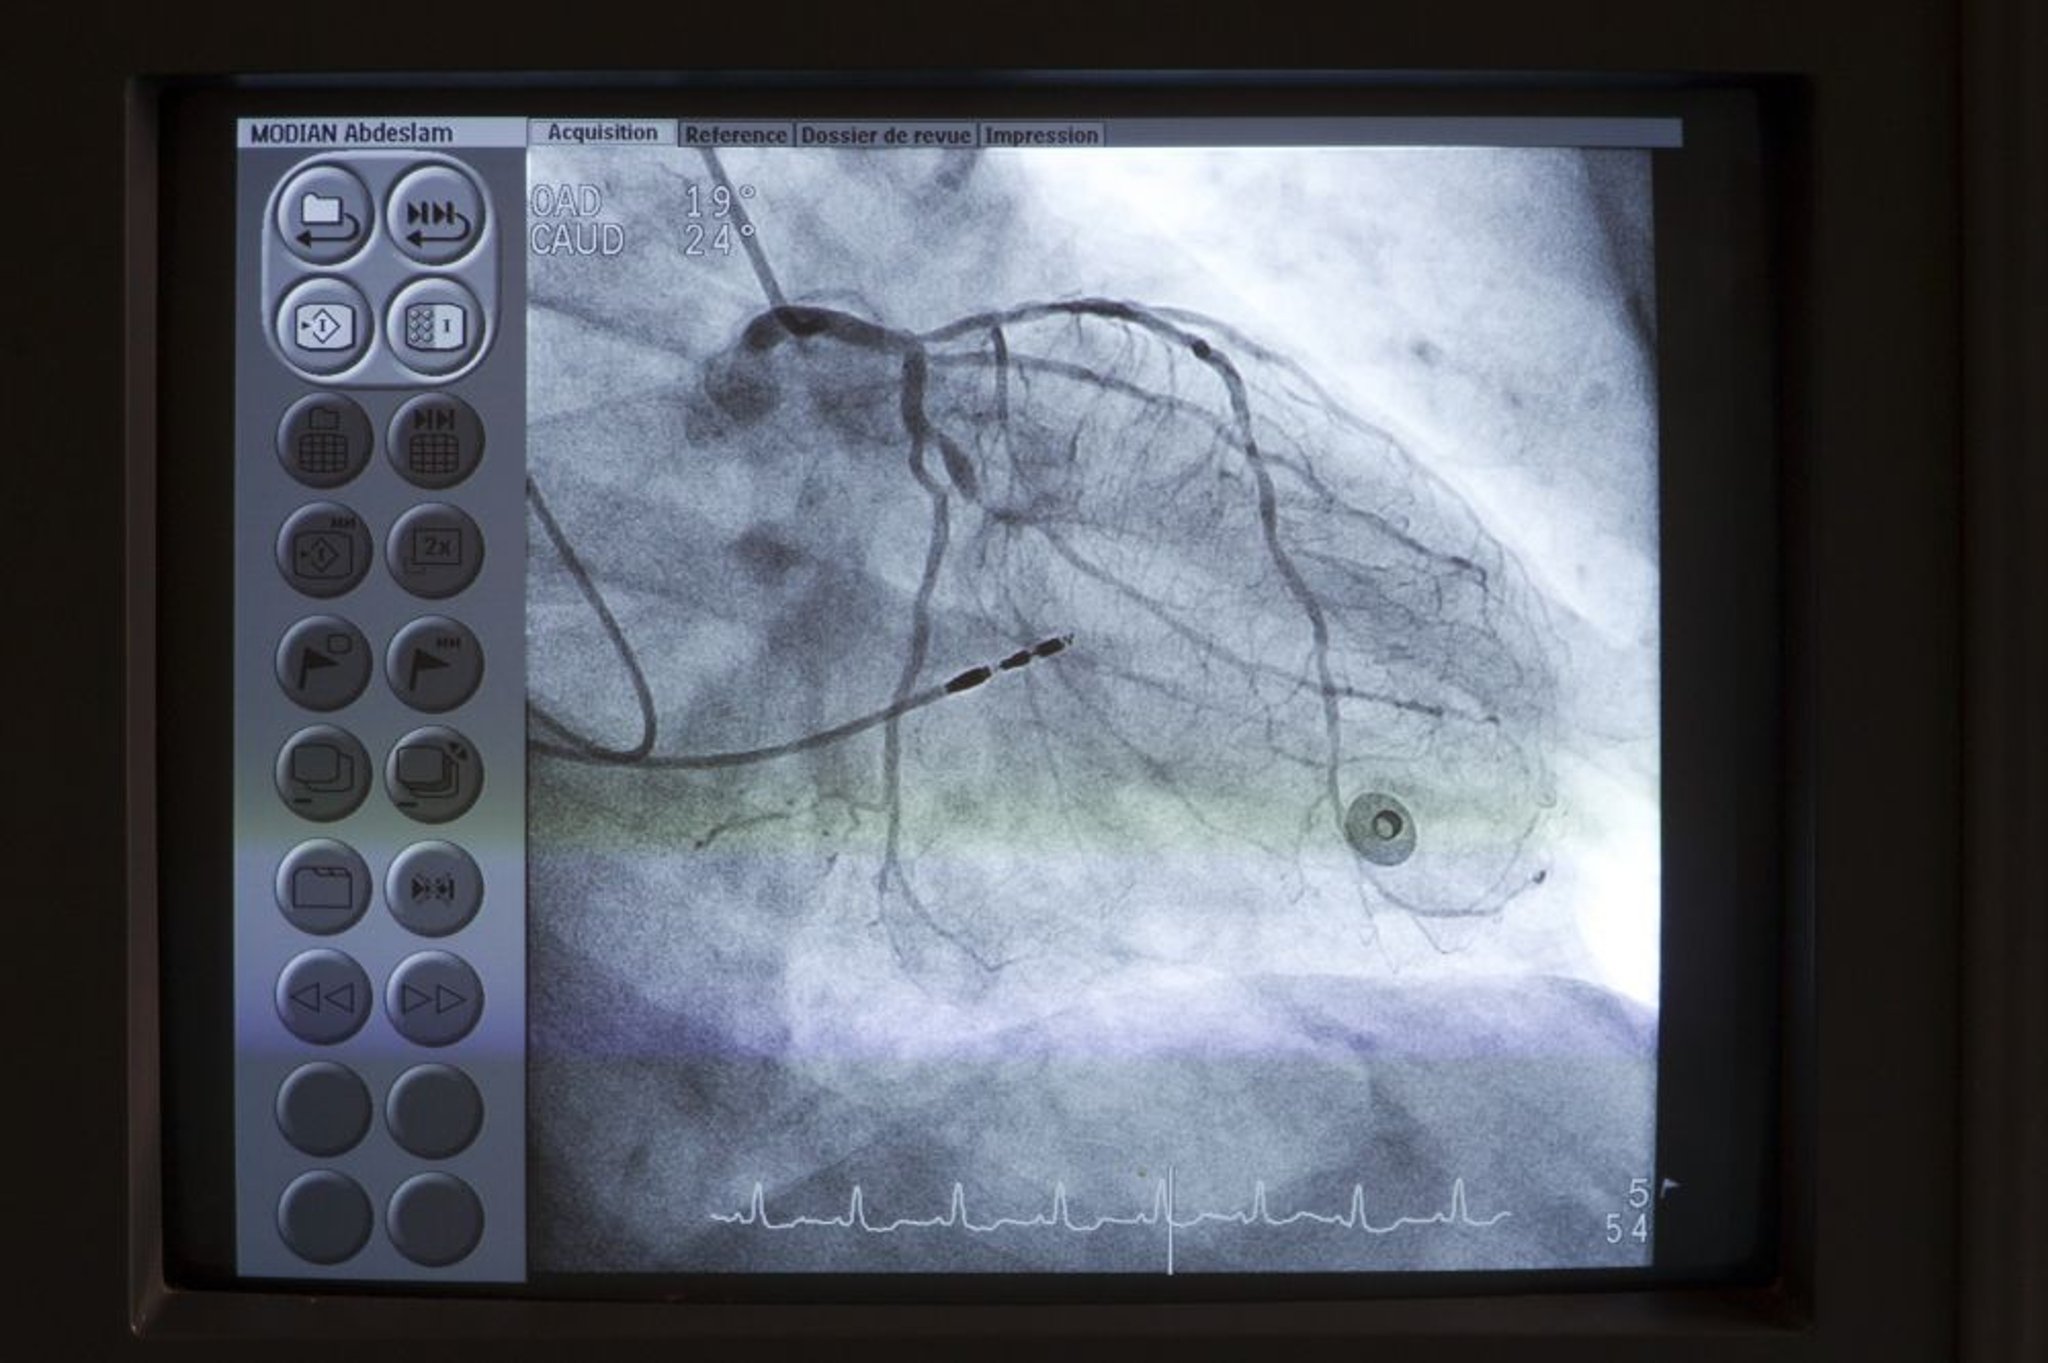

Un catetere (in alto a sinistra) è posizionato all'inizio dell'arteria coronaria principale sinistra. Il contrasto viene poi iniettato nelle arterie coronarie sotto fluoroscopia per rilevare eventuali anomalie come stenosi.

Astier/BSIP/SCIENCE PHOTO LIBRARY